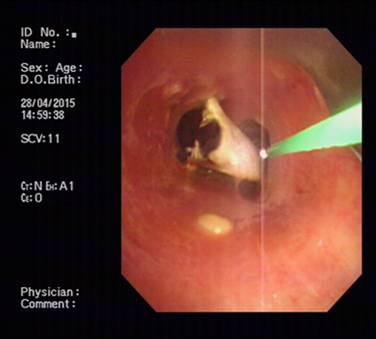

起初,因为没有什么感觉,胡某并不在意。3天后,胡某出现咳嗽气急症状,来到市内一家医院就诊。该院消化化、五官科医生经对他进行胃镜、喉镜检查后,却均未发现异常。由于咳嗽症状加剧呼吸越来越局促,4月27日,胡某经人介绍来到我院呼吸科就诊。经行纤维支气管镜检查后发现,胡某的气管壁黏膜上竟刺嵌着一枚长4.7厘米的巨大异物,经仔细观察,原来是一只蟹脚,于是当即将患者安排住院。患者入院后,该科在学科带头人、副院长俞万钧博士带领下,经过缜密全面的术前检查和评估后,决定用硬镜(硬质支气管镜)联合软镜(纤维支气管镜),对胡某实施钬激光粉碎异物术,以确保在异物清除过程中气管和声带等重要器官不被损伤。术中,负责手术的俞万钧博士小心翼翼地经支气管软镜将钬激光纤维导管插入,然后对准异物进行汽化消融,一点一点把打碎的蟹壳从患者的气管深处取出。由于手术没有一点损伤气管黏膜和出血,术后第2天,患者康复出院。

据俞万钧副院长介绍,钬激光是利用稀有元素钬而产生的脉冲式近红外线激光,波长为2140nm,恰位于水的吸收范围。它通过一种“钻孔效应”能汽化含水的异物如:动物贝壳、骨骼等,导致其表面和内部含有的水分在瞬间高度汽化膨胀,造成无数连续的微小爆破,并且这些微爆破又产生二次冲击波,于是异物如同豆腐碴般在双重微爆下由表及里层层崩解。据悉,联合使用硬质支气管镜和软质纤维支气管镜,采用钬激光取气管内异物在宁波尚属首创。(呼吸科 马坚)

图片1 钬激光粉碎蟹脚